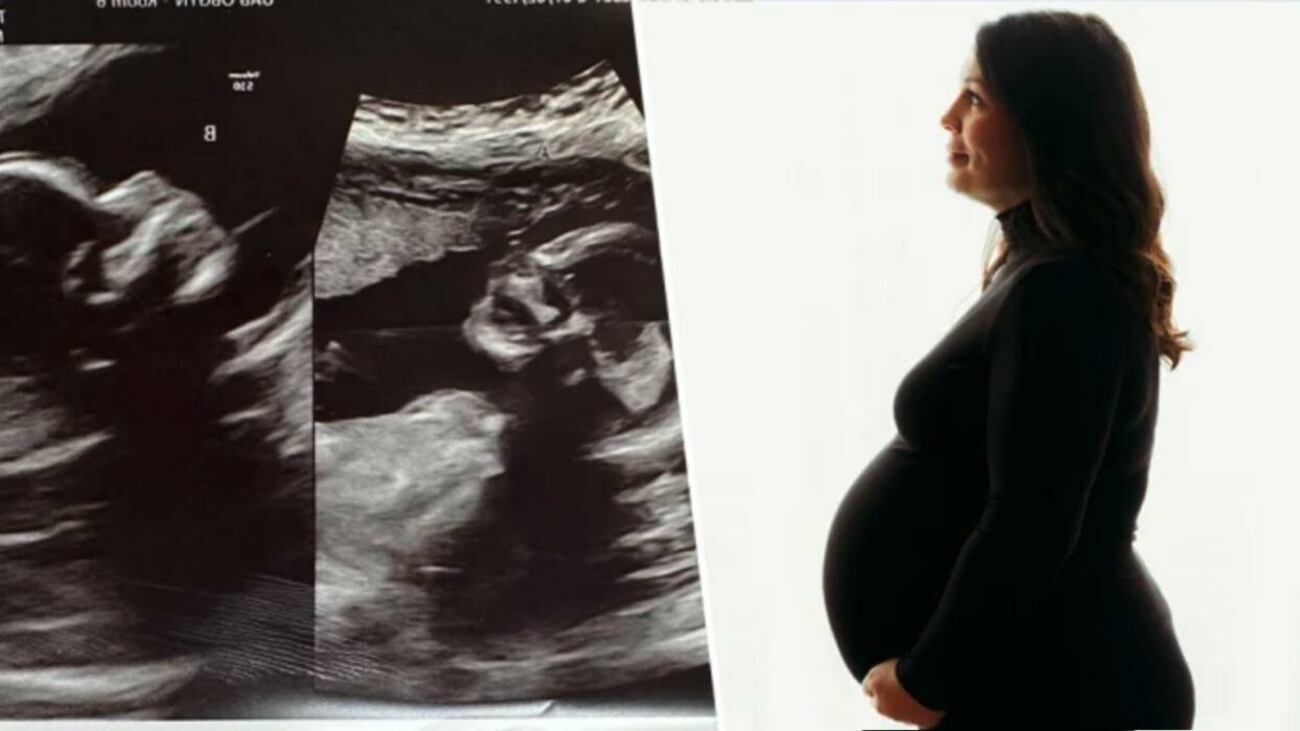

La protagonista de esta particular historia se llama Kelsey Hatcher, que nació con dos úteros y dos cérvix. Su sorpresa fue cuando se enteró que estaba embarazada de gemelos, informó WVTM, una filial local de la NBC.

Richard Davis, médico experto en embarazos de alto riesgo del Hospital de la Universidad de Alabama-Birmingham, dijo a la WVTM que “muy por debajo del 1 %” de las mujeres nacen con doble útero y doble cuello uterino. “Tal vez 3 de cada 1.000 mujeres podrían tenerlo. Y la probabilidad de tener un gemelo en cada uno es realmente una locura”.

Por esta condición, cuando Hatcher dé a luz, los médicos tendrán que tener mucho cuidado para controlar cada útero y determinar cuál se está contrayendo y si se están contrayendo juntos o por separado.